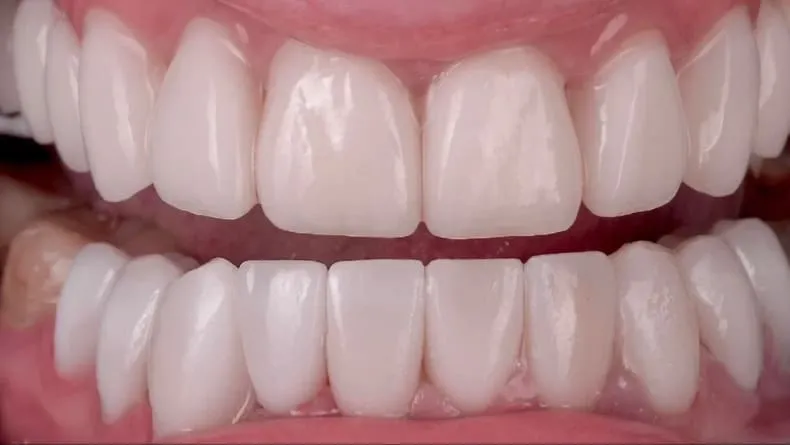

Author’s veneers